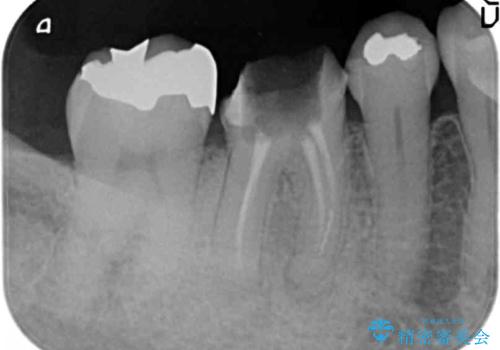

- 銀歯がダツリし、支える歯が破れている状態で抜歯を余儀なくされました。

短期間での咬合昨日の回復、手術を希望されなかったのでブリッジによる咬合機能回復を計画します。

かみ合わせが強いのでフルジルコニアクラウンベレッツァを用いたブリッジを製作。